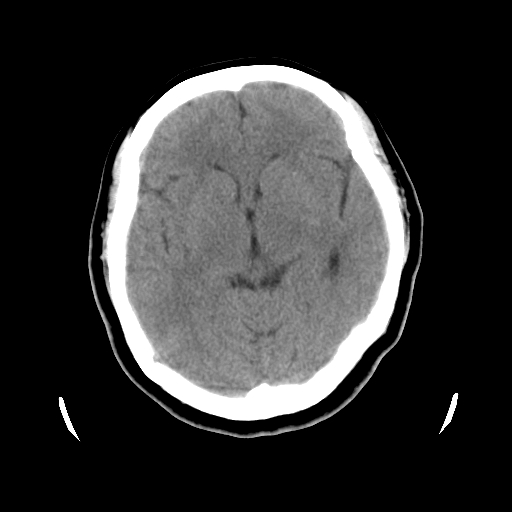

以下是引用cgf在2010-1-3 17:53:00的发言:[br]此病例多考虑:透明隔发育异常 透明隔囊肿可能性大;右侧基底节区(尾状核头)小片状低密度影考虑陈旧性腔梗[br][br]透明隔发育异常:包括透明隔间腔(第五脑室)、韦氏腔(第六脑室)、透明隔囊肿、透明隔缺如;前两者属于正常变异,后两者属于发育畸形;[br]透明隔间腔向下扩张形成韦氏腔;[br]有时透明隔间腔与透明隔囊肿很难鉴别;透明隔间腔间距一般不超过0.5cm,间距大于0.5cm时应考虑透明隔囊肿;[br]透明隔缺如为两侧脑室间隔缺如、融合成单脑室畸形,可伴有智力发育异常;[br][br]

以下是引用liaoqiang在2010-1-3 16:04:00的发言:[br]考虑侧脑室脉络丛囊肿?不除外变异的威氏腔。

以下是引用江广1996在2010-1-3 20:17:00的发言:[br]考虑变异的威氏腔。不除外侧脑室脉络丛囊肿.[br]透明隔囊肿大多数偏前,在侧脑室前角之间。